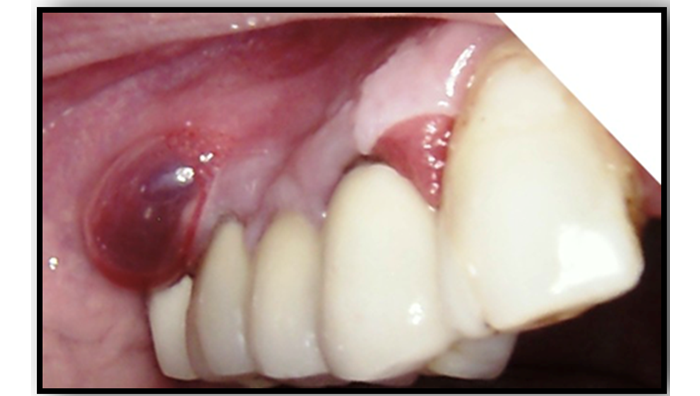

Figure-3. Ruptured bullae

Source: Photo is taken by us- clinical case, that we describe

After some days others lesions were presented in oral mucosa-Fig.2-a,b, fig.3

During the scheduled visit to dental office a 54-year-old male was diagnosed with bullae in vestibular aspect of right maxilla. He was reported to the outpatient Department of Oral and Maxillofacial surgery, FDM, MU - Sofia, with a chief complaint of bullae. He has no history of difficulty in swallowing food or any eyesight problems. On general physical examination there were not any complaints and findings. On intraoral examination, a solitary intact bullae measuring about 5 mm in diameter was present on the upper labial mucosa.(Fig.1.) No other bullae and vesicles were founded. Based on patient's history and clinical presentation, a provisional diagnosis of mucous membrane pemphigoid was considered. After the rupture of bullae it left large, superficial, ulcerated, and denuded areas of mucosa.